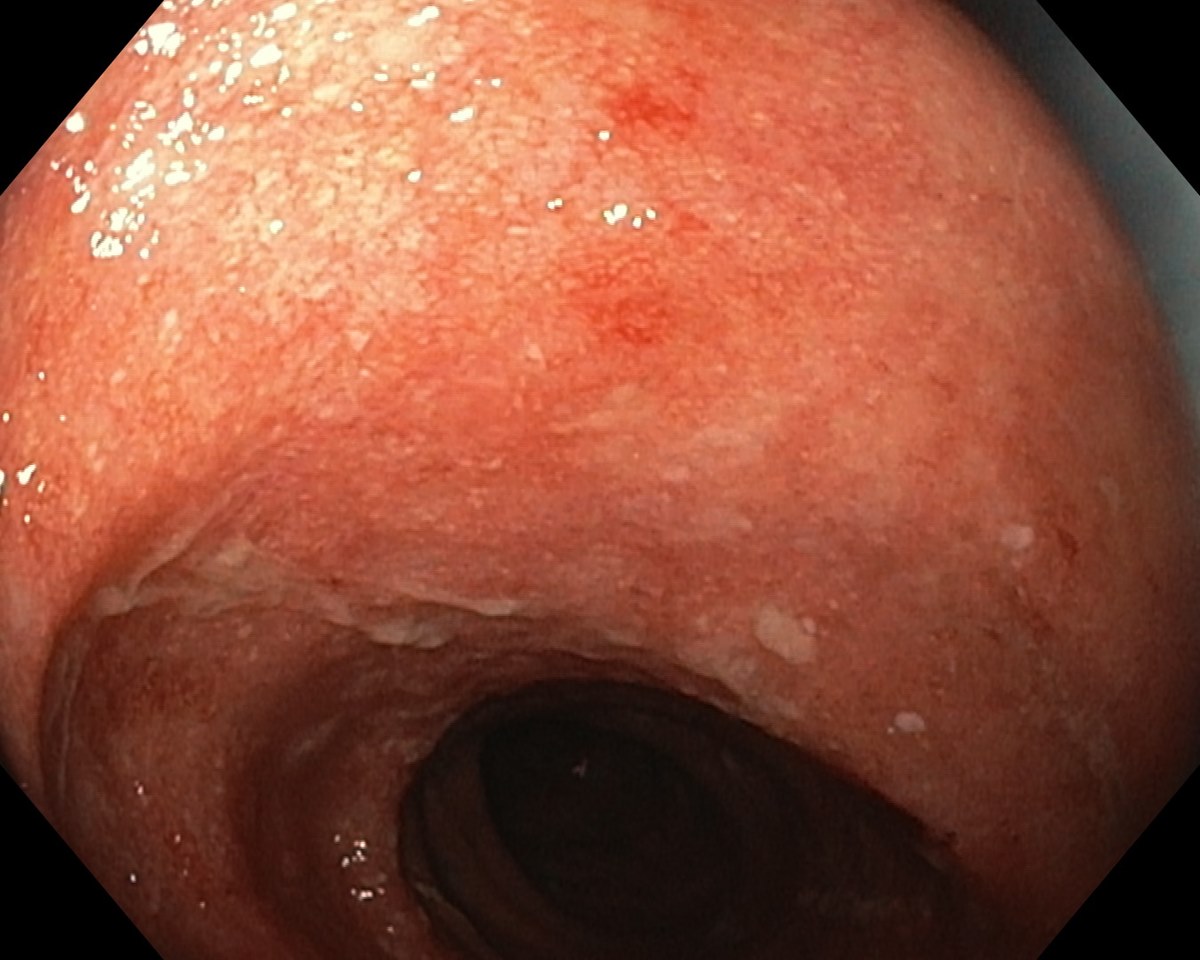

A Distal Ulcerative Colitis, Proctosigmoiditis Ulcerosa

A Distal Ulcerative Colitis.

A Distal Ulcerative Colitis